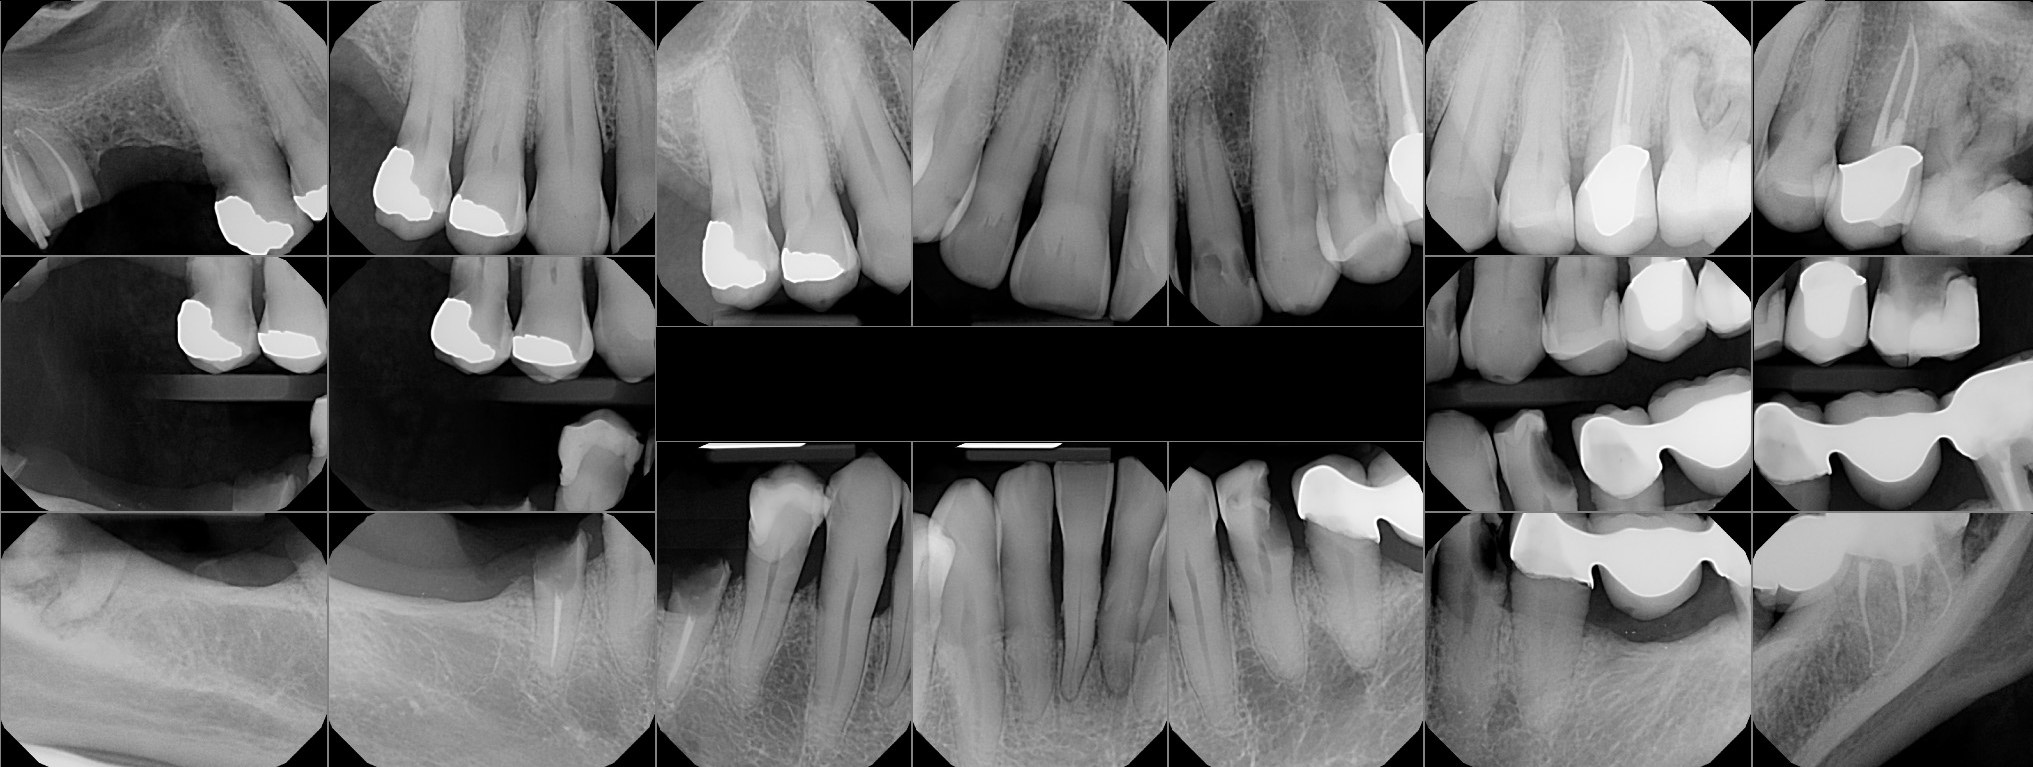

Auction images